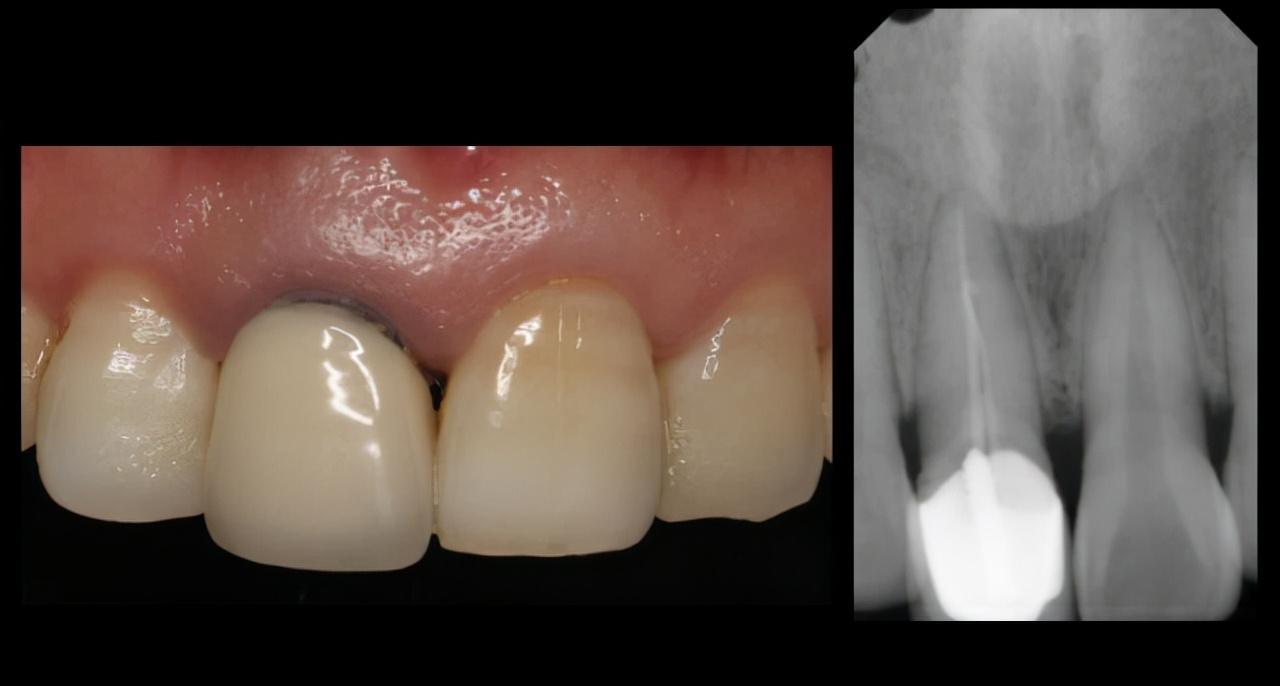

牙齿外伤分好几种情况,折断是其中一种,折断并暴露牙髓的牙齿在一定时间内是有可能“接”回去的!因为牙髓外面有一层牙周细胞膜,离开牙齿后不会马上失活,这时候我们要保证折断的牙齿没有受到二次伤害,比如干燥、过度清洁,就是不要拿纸巾去吸干水分、不要在水下面大力冲洗,更不要用肥皂、洗手液这类的东西去做清洁。

牙齿保存好了,下一步要做什么?半个小时之内找到一个靠谱的医生,有很大概率可以把断牙接回去!接回去的意思不止是说把断掉的部分像补牙那样安上,是在恢复牙齿外观的同时,“救活”这颗牙齿,而不是像根管治疗那样“杀死”牙神经,留下一颗脆弱的“死”牙齿。

“幸好遇到了诊所的医生,不然那颗牙用纸包着到医院也救不回来了 。”看着走开的邻居,我突然想起之前遇到的一个小姑娘,也是八九岁的年纪,她是从滑梯上摔下来把门牙磕断的,被我的同事遇到就带回我们医院。从牙齿的保管到后面院内的紧急处理都很顺利,医生跟家长解释了“断牙再接”这项操作。但是她妈妈对于“断牙再接”持怀疑态度,打电话联系了开诊所的“亲戚”后,亲戚告诉她,断了就断了,等孩子再大一点补一下就好了。然后她就把孩子带走了。

不良修复体